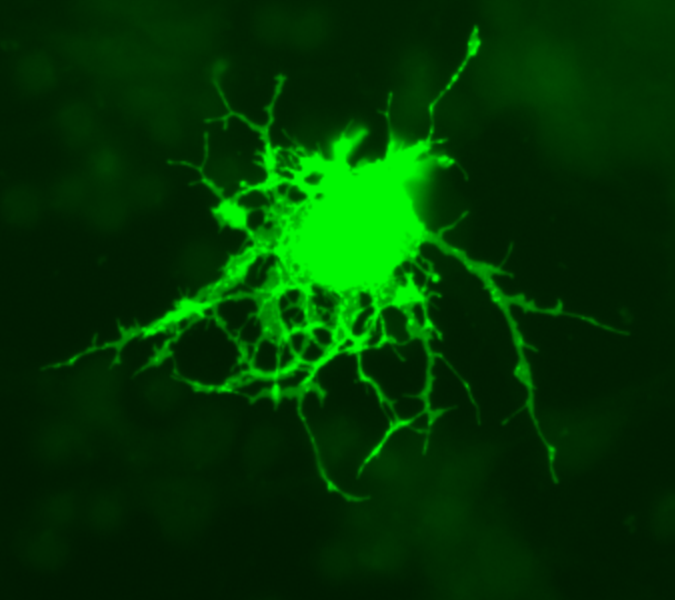

In MS the myelin is attacked by the immune system and may not be completely restored by myelin-producing cells (mature oligodendrocytes). The researchers discovered that the addition of Klotho protein to immature oligodendrocytes causes them to mature and manufacture proteins needed for the production of healthy myelin.

Image Source: The image of an oligodendrocyte is credited to Methoxyroxy at Wikimedia Commons and is licensed as public domain. Feel free to use.